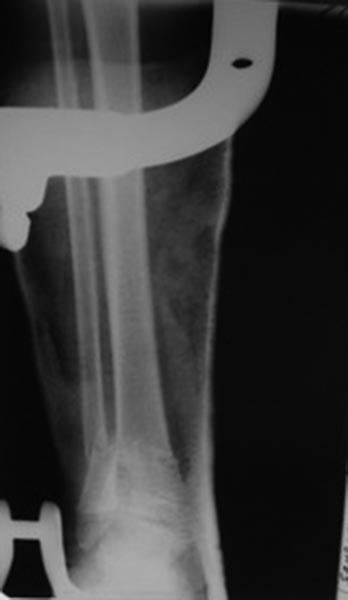

Переломы оскольчатые обеих бёдер в н/3, открытые. Раны ушиты в отличном

состоянии.

Голень там тоже сломана в н/3 обе кости. Снимок голени в боковой

проекции сделан не был.